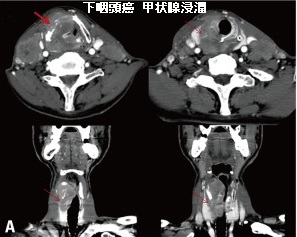

下咽頭癌は、

- 高齢男性に多い

- 扁平上皮癌

- 喉頭がん・食道がんと同じく飲酒と喫煙がリスクファクター

特に下咽頭癌と食道癌は重複しやすいので、一方の癌が見つかったときはスクリーニング検査が必要。 - 頸部リンパ節転移を生じやすく、無痛性の徐々に増大する頸部腫瘤で発症する事がある

などの特徴があります。

下咽頭癌の治療は、

- 抗がん剤の化学療法

- 放射線療法

- 手術摘出;喉頭を合併切除する事もある

の単独か併用。